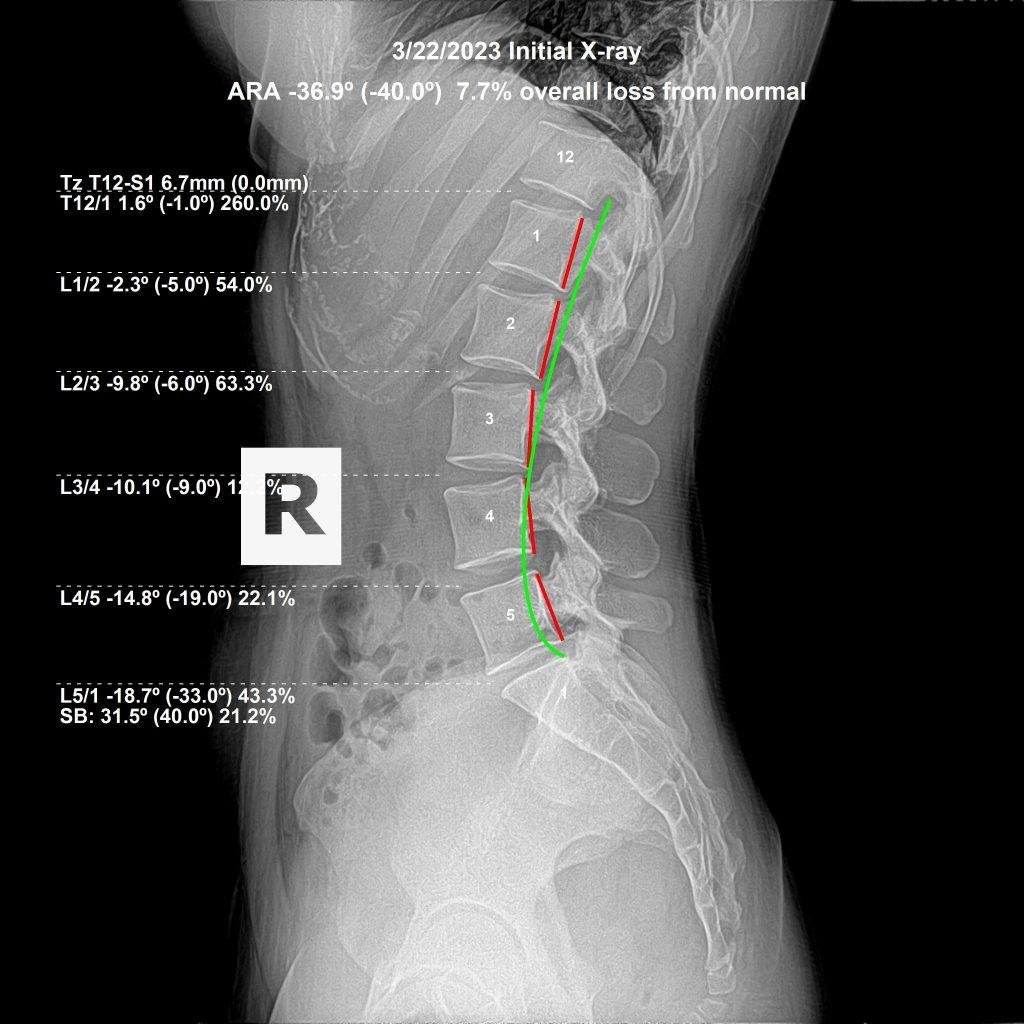

X-ray analysis revealed reversed cervical lordosis, anterior head displacement, and lumbar curve reduction. The before/after X-rays below document the measurable structural change after a structured correction plan.

Before cervical X-ray — reversed curve, anterior head displacement — Royal Palm Beach FL Cervical — Before Reversed cervical curve, anterior head displacement, nerve pressure at multiple segments

After cervical X-ray — cervical lordosis restoring — Dr. Rochet Royal Palm Beach Cervical — After Cervical lordosis restoring, reduced nerve pressure, measurable structural improvement

Actual patient X-rays. Results vary individually.